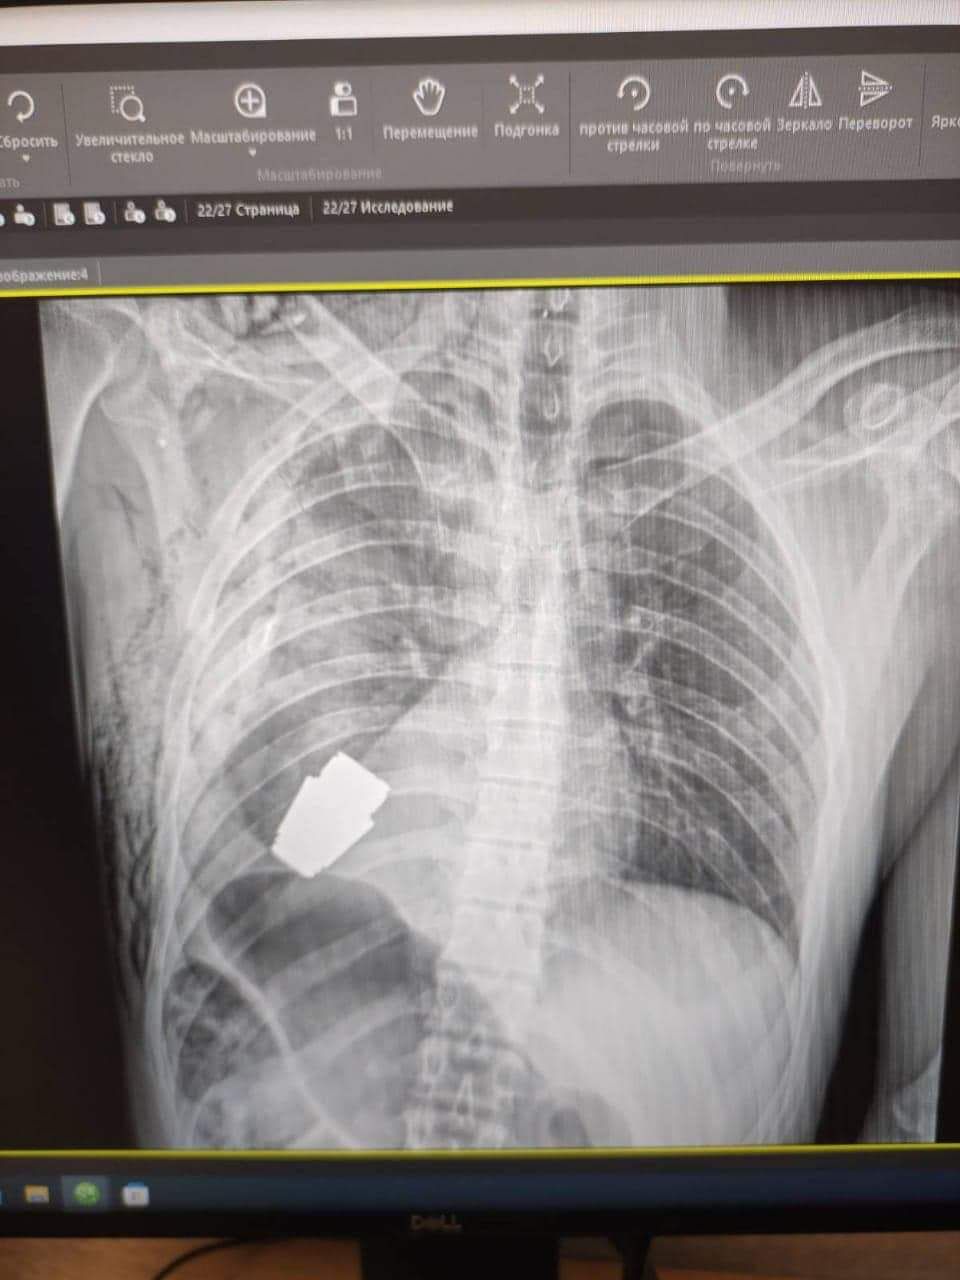

По словам медиков, военные врачи провели уникальную операцию. Им удалось вытащить из грудной клетки бойца гранату ВОГ, которая не разорвалась.

Процедуру проводили без электрокоагуляции, потому что боеприпас мог сдетонировать в любой момент. Врачей страховали саперы, которые были рядом все время. Однако операция прошла успешно и гранату убрали из тела бойца. Военный чувствует себя хорошо и проходит реабилитацию.